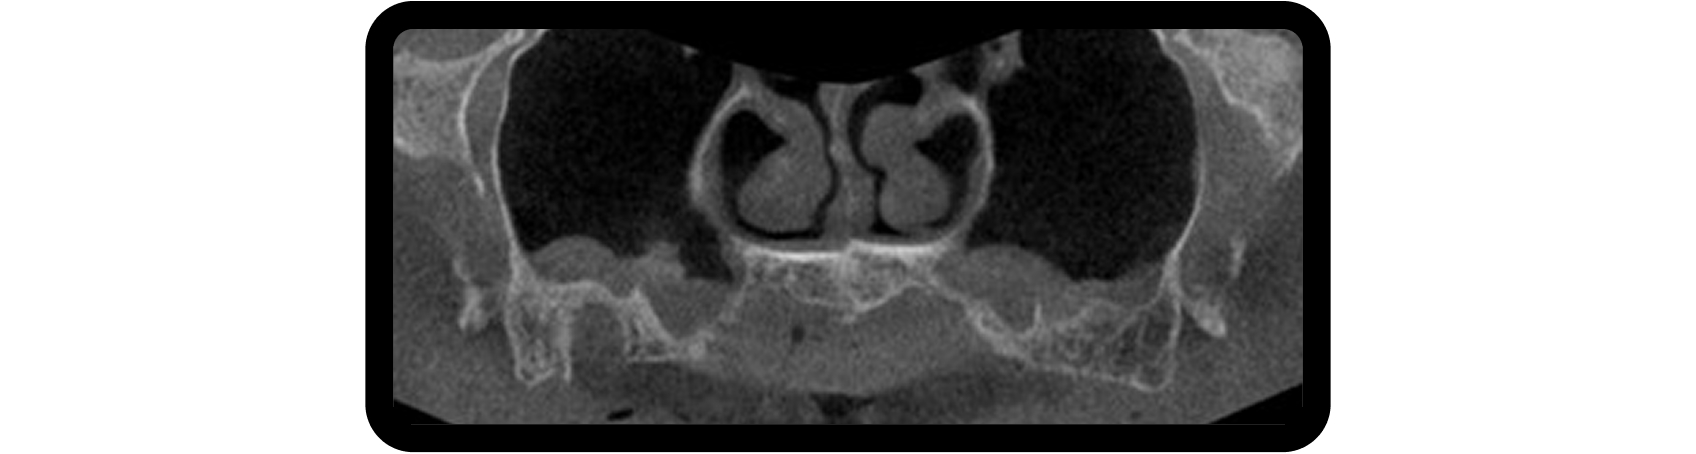

Bilateral sinus augmentation was required to support a six-implant, screw-retained zirconia restoration. A CBCT scan revealed radiolucencies in both maxillary sinuses, prompting referral to an ENT specialist before proceeding (Fig. 4).